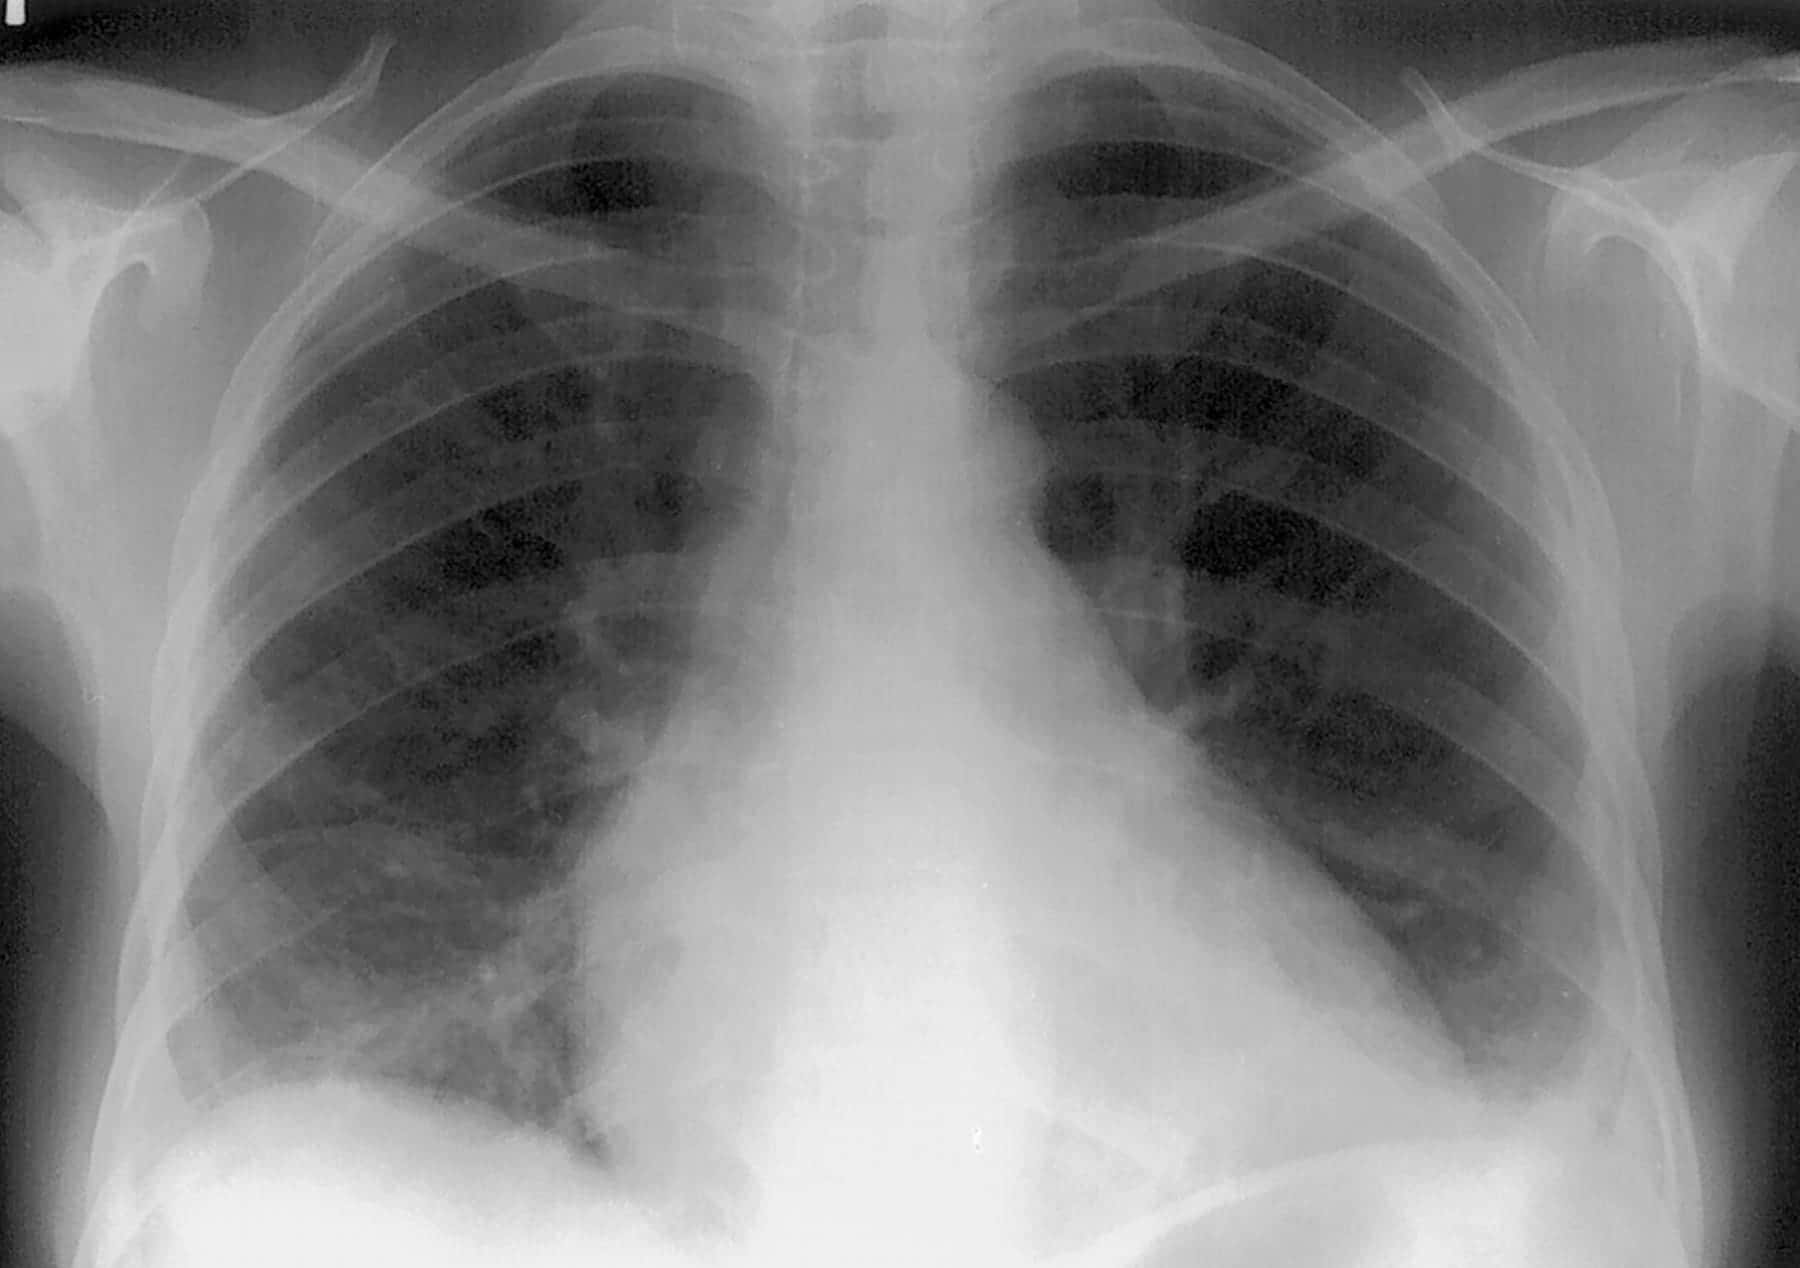

This case involves a sixteen-year-old male who presented to the ER with fever, cough, shortness of breath, and intense chest pain. The boy’s past medical history included sickle cell anemia and recurrent infections. An x-ray was performed and he was diagnosed with pneumonia. Antibiotics and intravenous fluids were administered to him for a day. The next day the patient’s oxygen saturation declined to 65% and he still experienced fever and chest pain. He was given pain medications and received continuous positive airway pressure (CPAP). His oxygenation level continued to decline until he lapsed into a coma. After being resuscitated for twenty minutes, the boy regained consciousness. Once stabilized, it was evident that he sustained brain injuries as a result of oxygen deprivation. He was discharged once he was able to breathe independently. The months following hospitalization, the boy was unable to perform rudimentary tasks such as feeding and dressing himself, and formulating clear sentences. His teacher reported that his reading and writing level was at a third-grade level and he was unable to keep up with his peers. He required homeschooling, occupational therapy, and physical therapy. His pediatrician noted that he believed the boy experienced acute chest syndrome. This diagnosis was not made by the ER.

This emergency medicine team failed to make the diagnosis of acute chest syndrome, a serious complication of sickle cell anemia. Acute chest syndrome is a condition within the pulmonary vasculature that results from deoxygenation of hemoglobin. This deoxygenation causes the blood to sickle and occlude these vessels. Patients aged ten to nineteen will most commonly develop acute chest syndrome after an infection. The diagnosis is based upon the presence of a new pulmonary infiltrate with chest pain, temperature > 38.5 degrees Celsius, tachypnea, wheezing, cough or increased work of breathing, and hypoxemia. Due to the seriousness of this condition, this boy should have been monitored more closely. This patient was properly managed with intravenous fluids, antibiotics, pain medications, and respiratory assistance. However, exchange transfusion was never put in place. This intervention is critical because it addresses the most serious complication of this syndrome; hypoxemia. Prolonged hypoxemia in this case resulted in permanent neurologic damage. This could have been avoided had the transfusion been initiated.